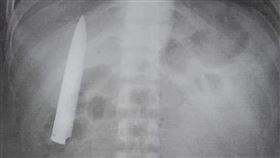

扯!醫師亂縫 10公分刀插胸逾1年

實在很誇張!菲律賓一位男子在去年1月,遭受數名少年持...

2021/03/27 13:11